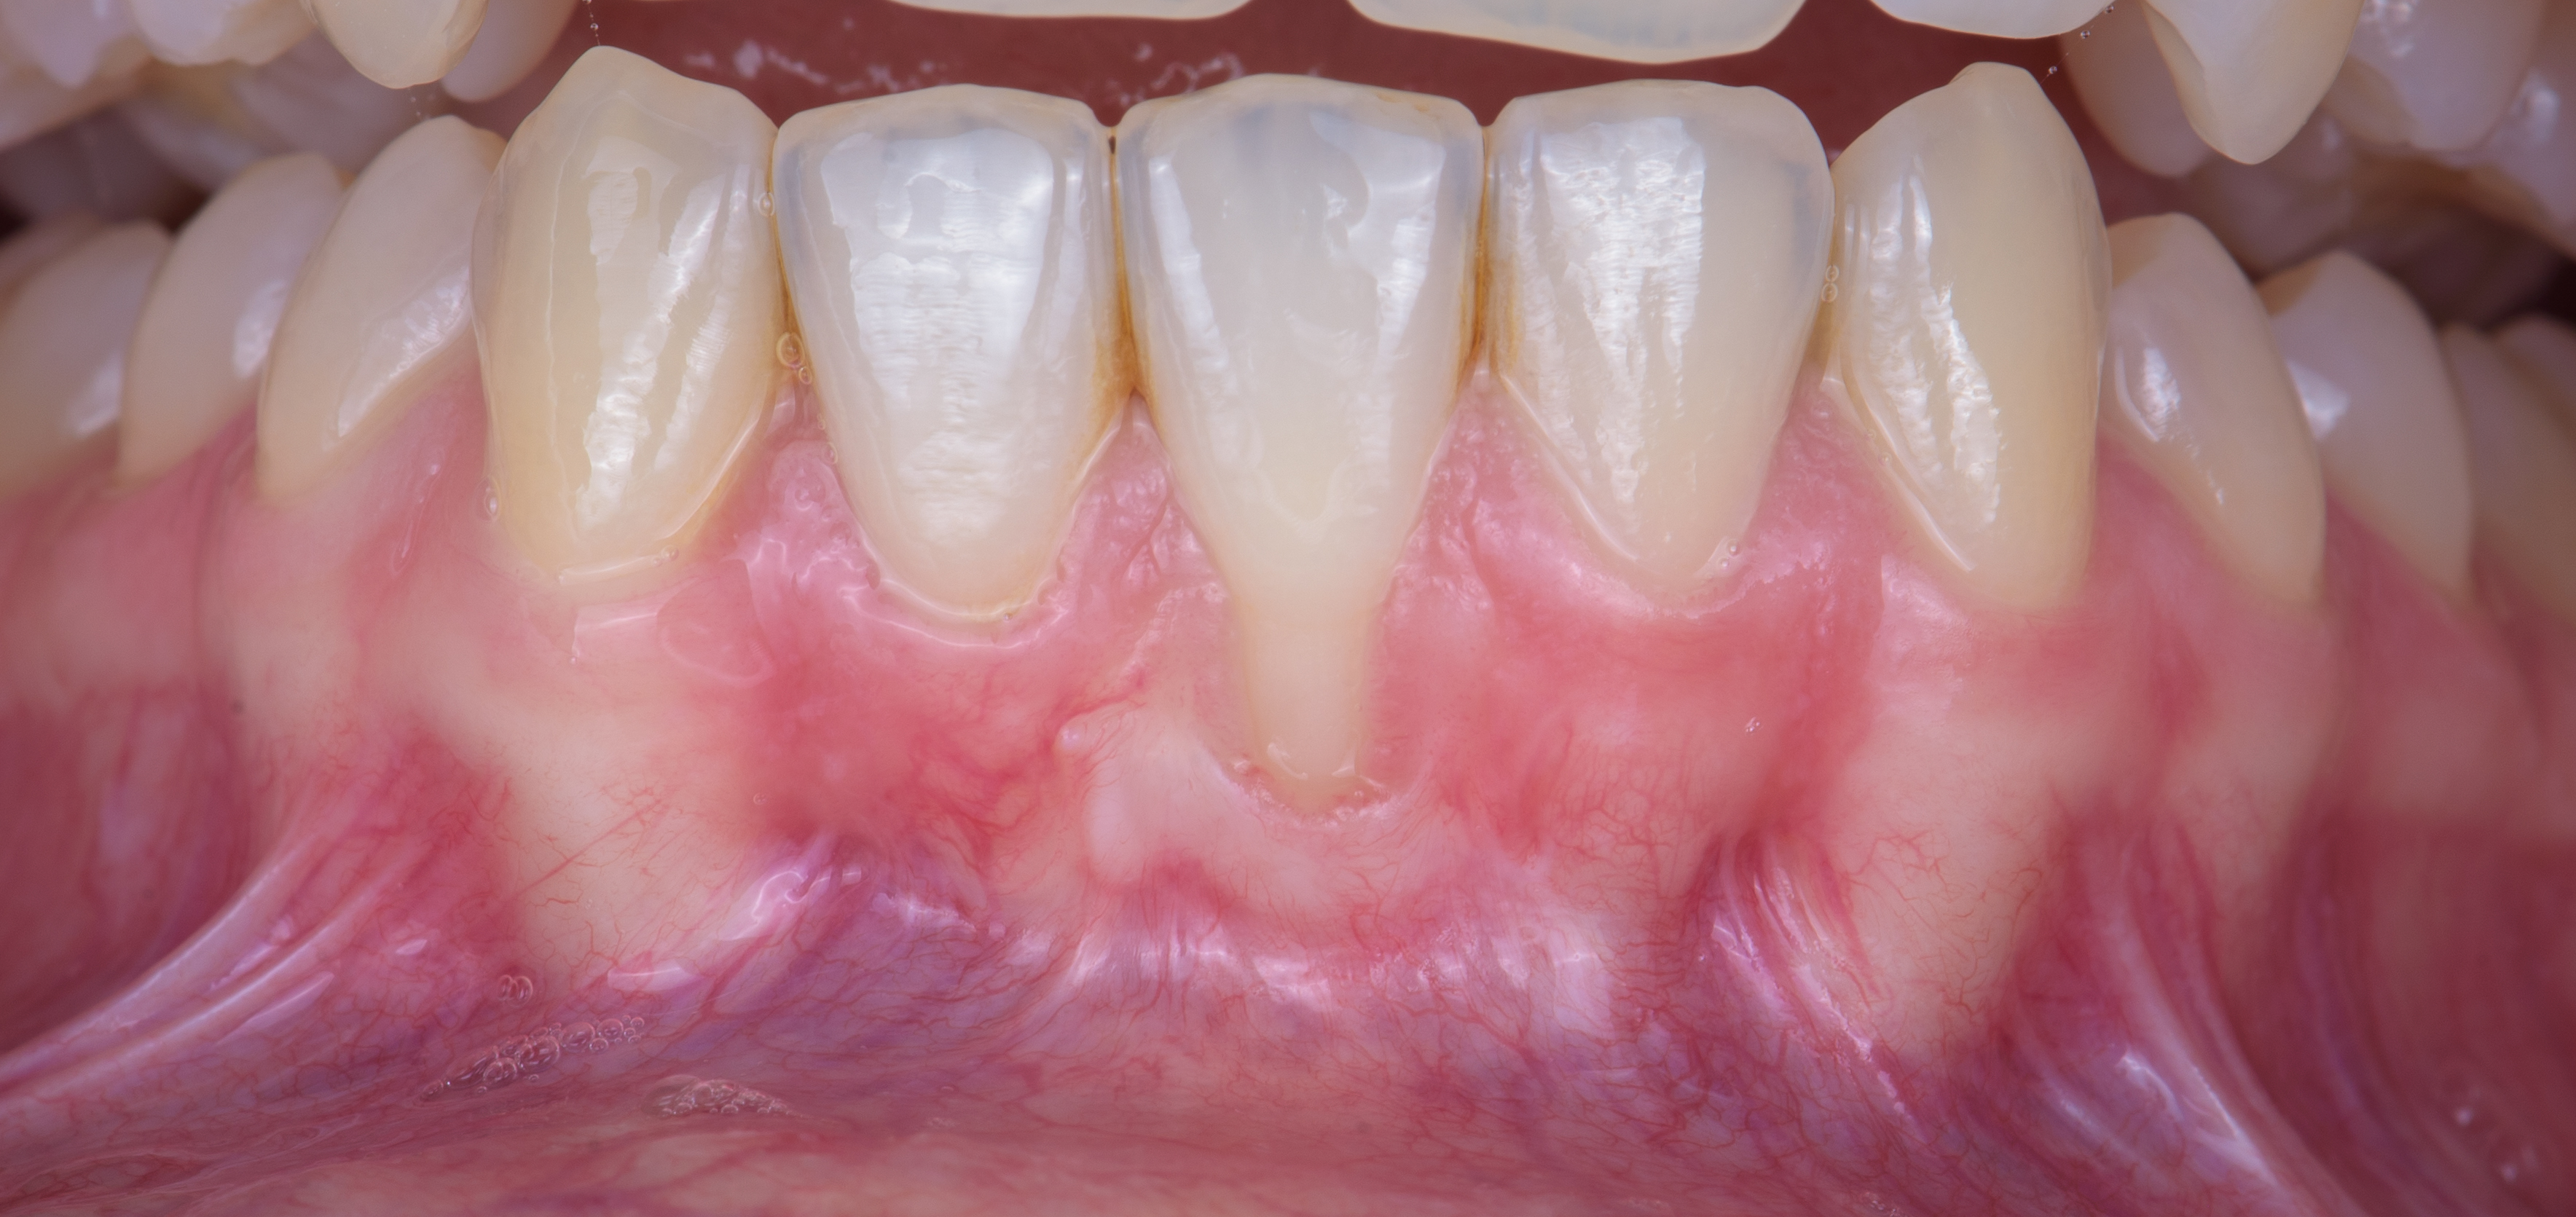

Master recession coverage in upper and lower teeth

Enhance skills in mucogingival surgery

Manage the soft tissue in aesthetic and non-aesthetic regions

Recession coverage for aesthetic or functional concerns.